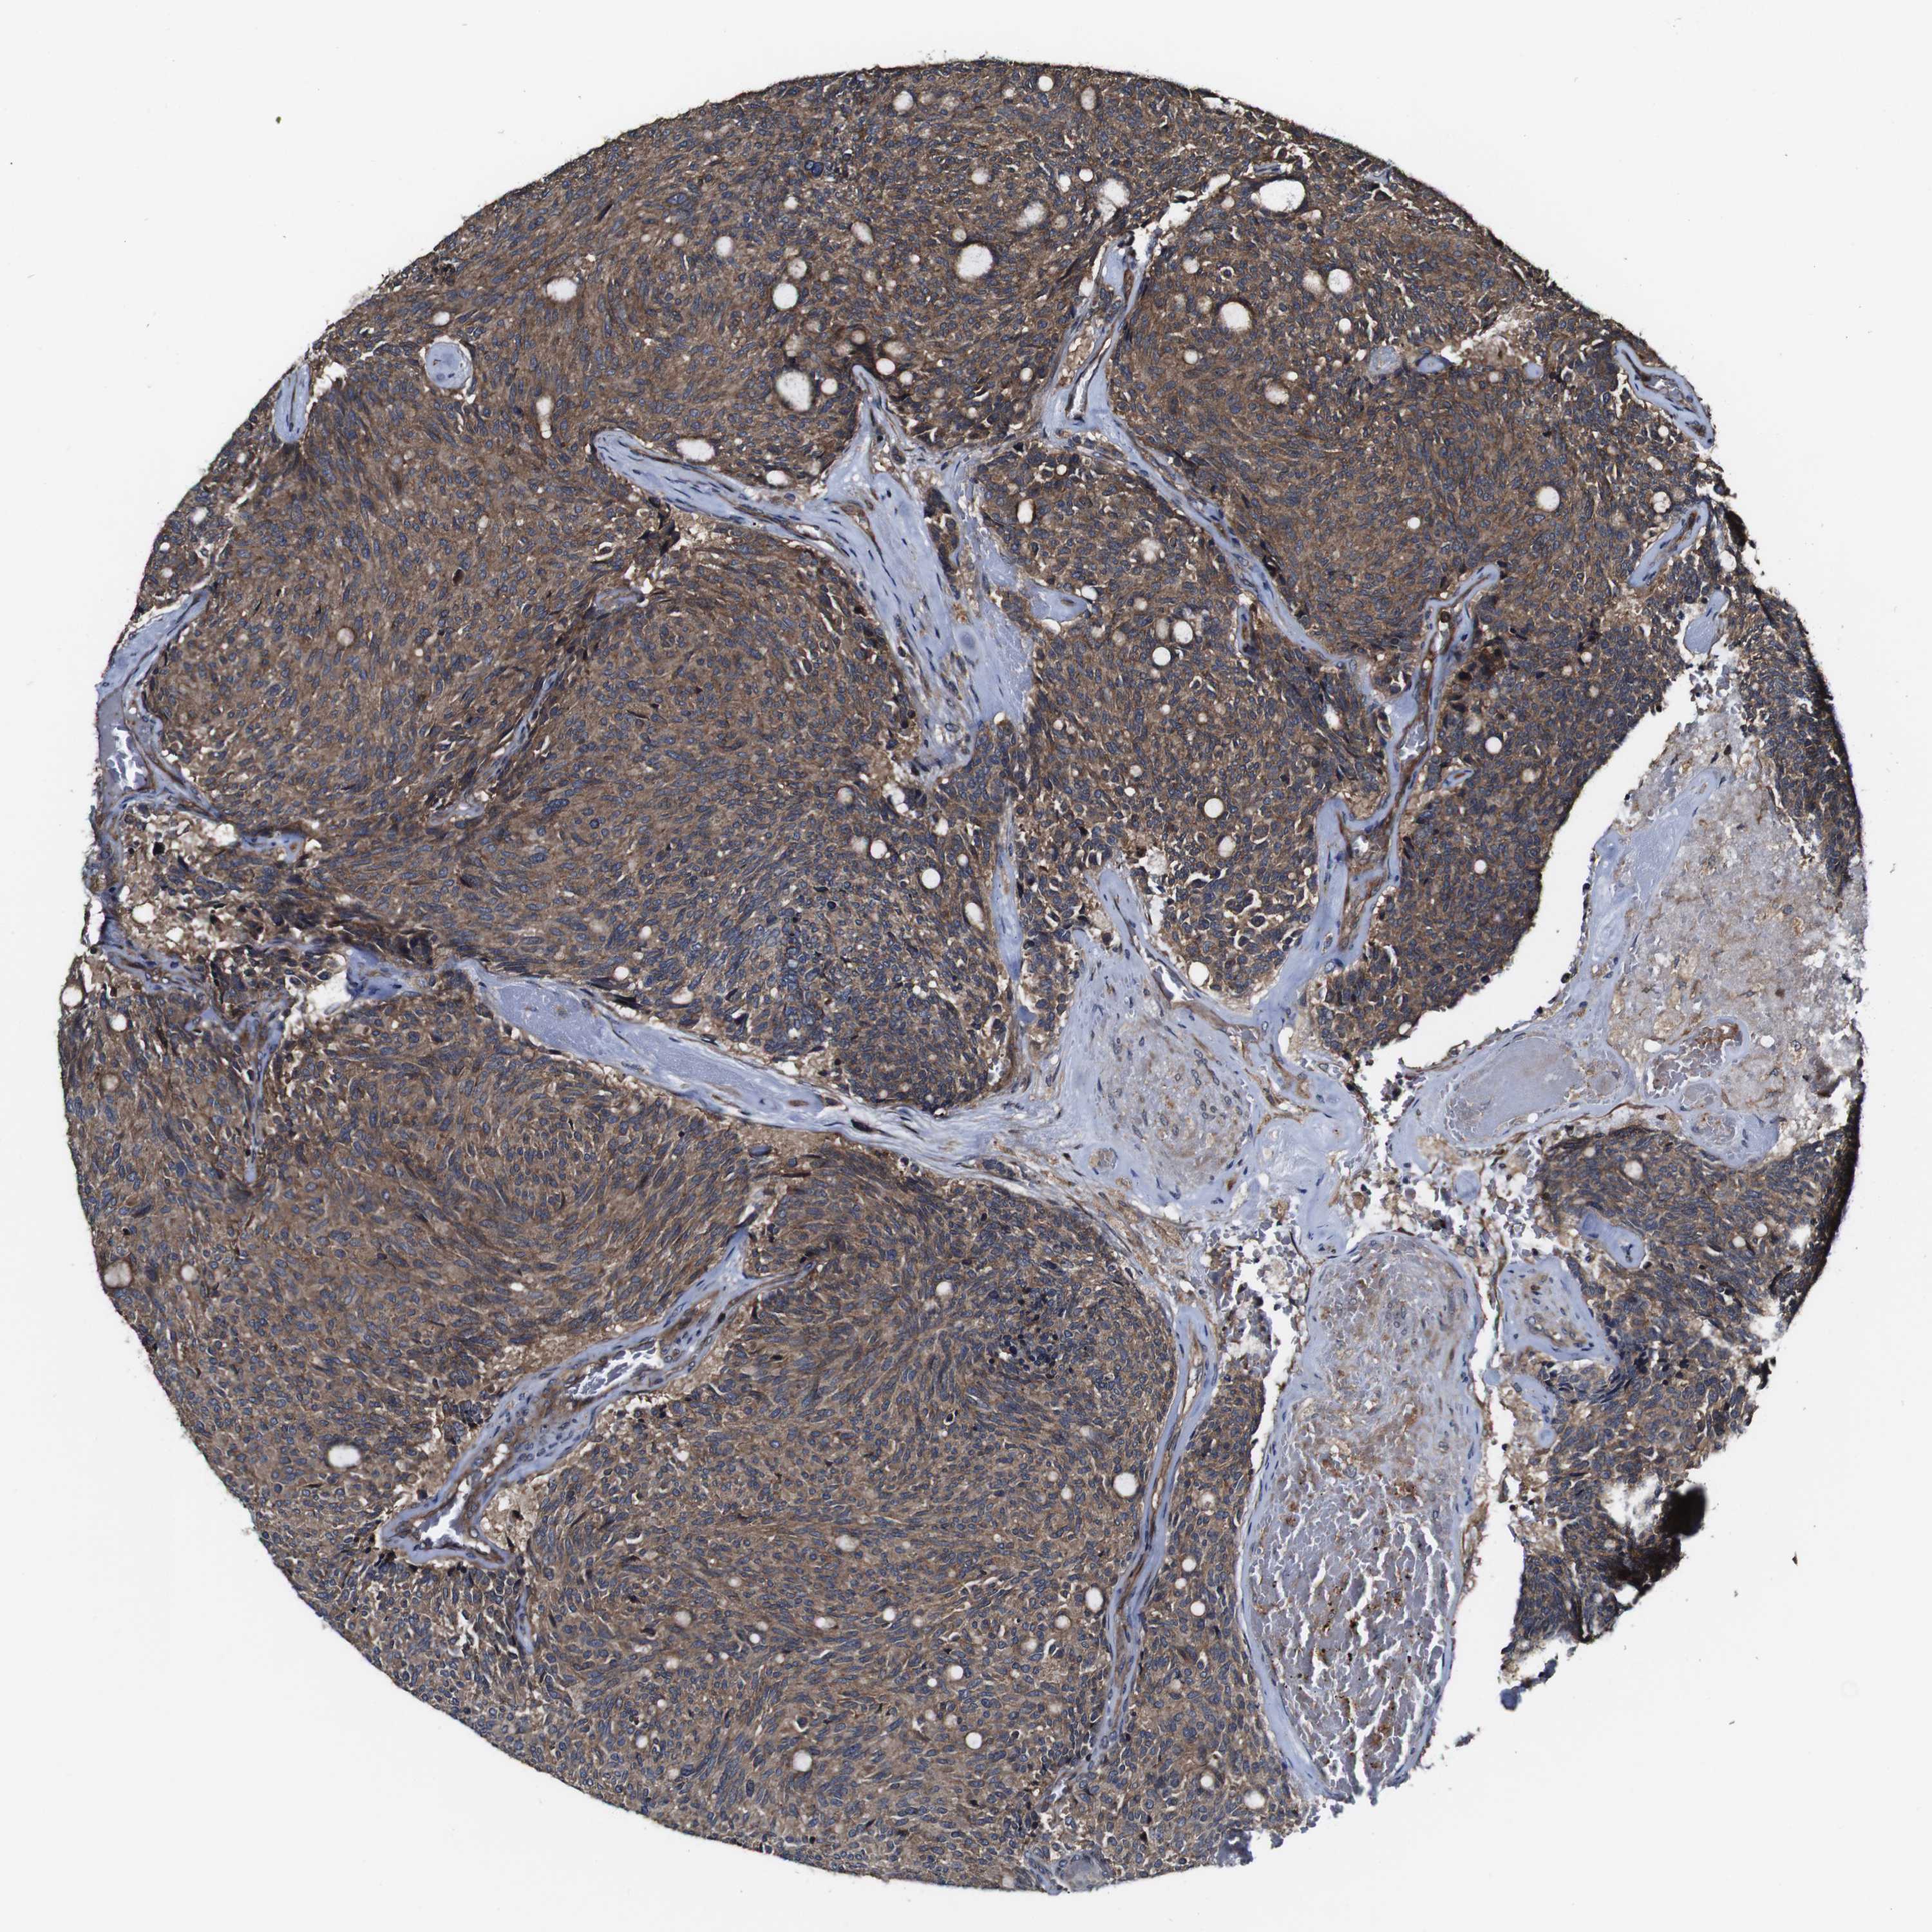

CARCINOID - Protein expressioni

A mouse-over function shows sample information and annotation data. Click on an image to view it in a full screen mode. Samples can be filtered based on level of antibody staining by selecting one or several of the following categories: high, medium, low and not detected. The assay and annotation is described here.

Each image is clickable and will lead to virtual microscopy that enables deeper exploration of all samples and also displays staining intensity scores, fraction scores and subcellular localization as well as patient and tissue information for each sample.

Antibody HPA012128

Staining

High

Intensity

Strong

Quantity

>75%

Location

Nuclear

Carcinoid, malignant, NOS